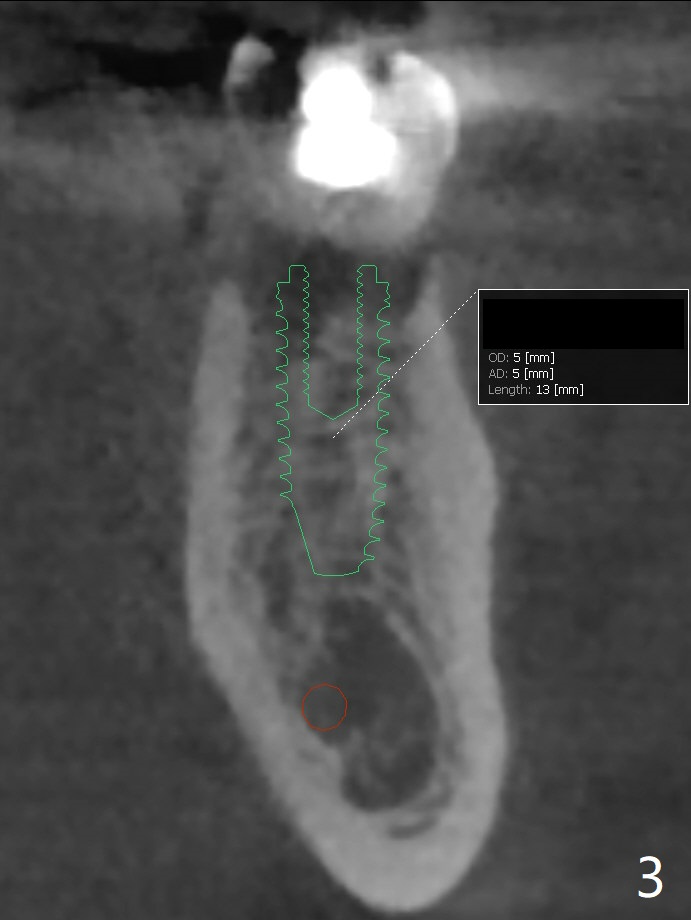

A 54-year-old man has crack at the tooth #19 (Fig.1). The pain gets worse when he returns to home country. The tooth is extracted without bone graft. Four months later, the buccolingual width reduces from 10.1 mm to 5.6 mm (Fig.2). A shorter implant (13 vs. 10 mm) has to be placed and also deeper (compare Fig.3,4) with higher chance of screw loosening.